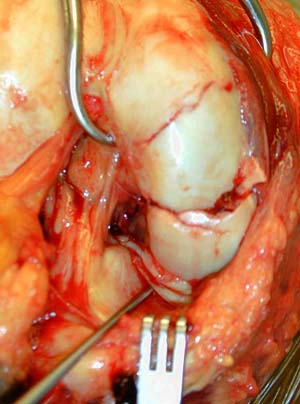

Около двух лет назад оперировали подобный перелом у женщины лет 45, с момента травмы до обращения к нам прошло около 1,5 месяцев. Выполнили открытую репозицию, остеосинтез компрессирующими спонгиозными винтами. Во время операции столкнулись с проблемой: так как задний фрагмент сместился вверх, а его суставная поверхность основная нагружаемая часть мыщелка, то вся нагрузка по оси пришлась на суставную поверхность переднего отломка и возник импрессионный перелом с вдавлением ло 1 см по высоте. После элевации хряща и сухондральной кости пришлось делать костную пластику.Результат и рентгенологический и функциональный через 6 мес был хороший. Если найду Р-граммы выложу

В данном случае предпочтителен парапателлярный доступ, где необходимо создать лучший обзор к мыщелку. После остеотомии и репозиции фиксацию надо проделать поперечными винтами и дополнительно задней antiglade plate - сделанной из 1/3 tubular plate.

Здесь представлены различные варианты фиксации перелома, а также снимки комбинации перелома с повреждением хряща (12-19). Пластика хряща OsseoFit и установка custom made plate.